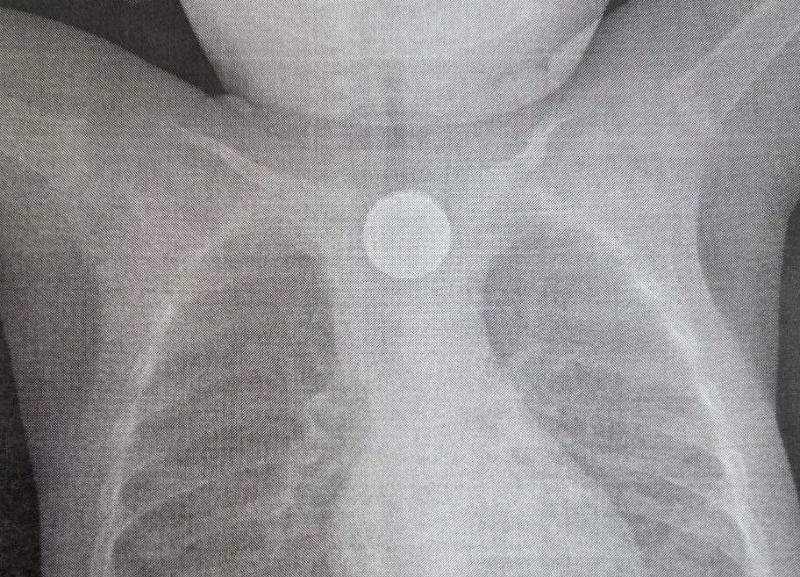

Врачи удалили из пищевода при помощи внутрипросветной эндоскопии 2-рублевую монету и литиевую батарейку. Она, находясь в пищеводе, вызвала химический ожог слизистой оболочки 3-й степени.